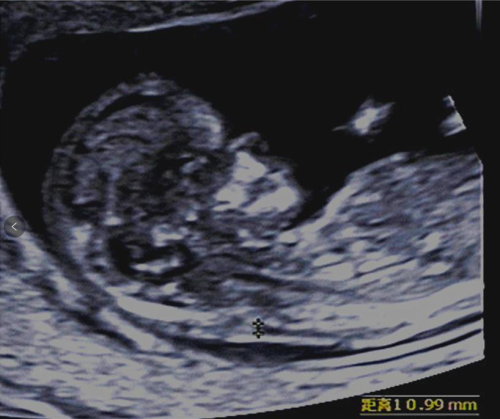

孕11-13周+6天要做一项重要的检查——颈项透明层厚度(NT)检查。随着“二孩”政策开放,高龄孕妇数量明显增多,早期NT检查显得特别重要。NT的异常增厚与胎儿畸形尤其是染色体异常有着密切的关系。NT检查适宜的孕周是11-13+6周,也就是头臀长在45-84mm之间。

这次检查除了NT的测量外,还需要观察一些软指标,如胎儿鼻骨是否存在、静脉导管血流频谱等,来综合判断胎儿有无染色体异常的风险。同时结合母体血清学检查,染色体异常宝宝的检出率可达90%以上。另外,这个阶段也能对胎儿的大体结构作一个初步的检查,对于一些严重的畸形早诊断、早处理,大大减轻孕妇身体及心理伤害。早孕期超声可以筛查出的胎儿畸形包括:无脑儿/露脑畸形,胎儿水囊瘤,腹壁畸形如脐膨出、腹裂/严重的内脏外翻,严重的肢体残缺等比较明显的畸形。而对于双胞胎宝宝的妈妈来说,这个时期的检查还有一个很重要的事情,就是确定双胎妊娠的绒毛膜性质,这对于将来中、晚孕期的检查以及临床医生的处理方法至关重要。

我科拥有先进的四维彩超设备,让准妈妈们在早孕期也能够观察到宝宝可爱、萌萌的样子。